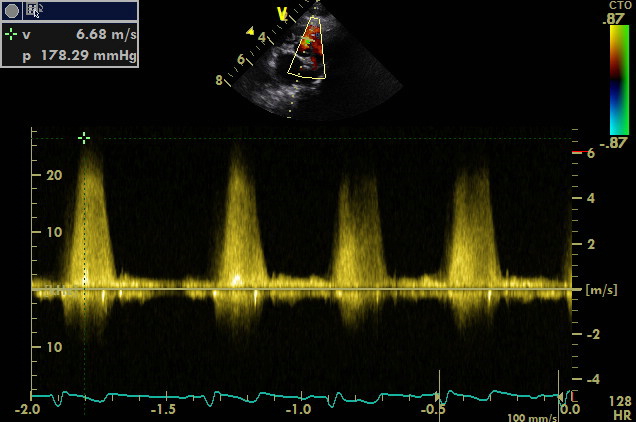

gradiente transventricolare di 178 mmHg questo e’ un pattern restrittivo compatibile con basse pressioni nel cuore di destra da considerare un bene per il soggetto ,gradienti minori indicano innalzamento delle pressioni nel ventricolo destro .